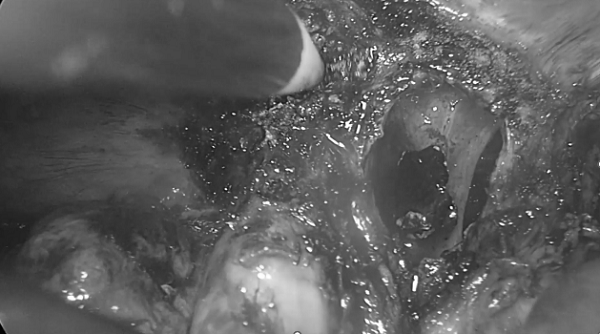

1.切除胆囊

2.胆管断端